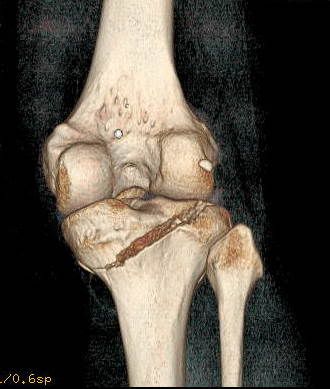

I had a tibial plateau fracture. Surgery with a plate and 10 screws to repair.